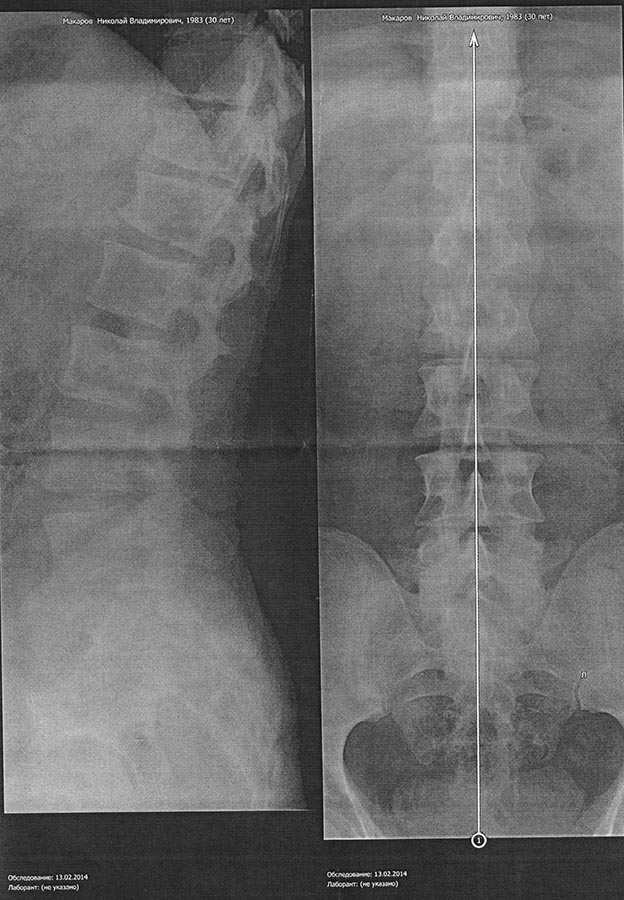

Жалуюсь на постоянные боли в пояснично-крестцовом отделе. Прикладываю снимок в двух проекциях. Мне 30 лет, рост 168, вес 70 кг. Снимали в лежачем положении. Хочется выслушать мнение специалистов.

Врач травматолог - тот самый, который "не углядел" 20 лет назад у меня перелом в нижнем грудном отделе. Вечили лишь перелом подвздошной кости таза. Доверия к нему теперь нет. Его диагноз - посттравматический остеохондроз. 5 лет периодически мне проводят курсы лечения диклофенаком. Боюсь за свою печень.